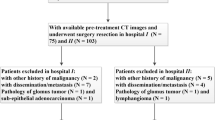

A total of 151 pathologically confirmed 1–2-cm gGISTs from seven institutions were identified by contrast-enhanced CT scans between January 2010 and March 2021. A detailed description of EUS morphological features was available for 73 gGISTs. The association between EUS or CT high-risk features and pathological malignant potential was evaluated. gGISTs were randomly divided into three groups to build the radiomics model, including 74 in the training cohort, 37 in validation cohort, and 40 in testing cohort. The ROIs covering the whole tumor volume were delineated on the CT images of the portal venous phase. The Pearson test and least absolute shrinkage and selection operator (LASSO) algorithm were used for feature selection, and the ROC curves were used to evaluate the model performance.